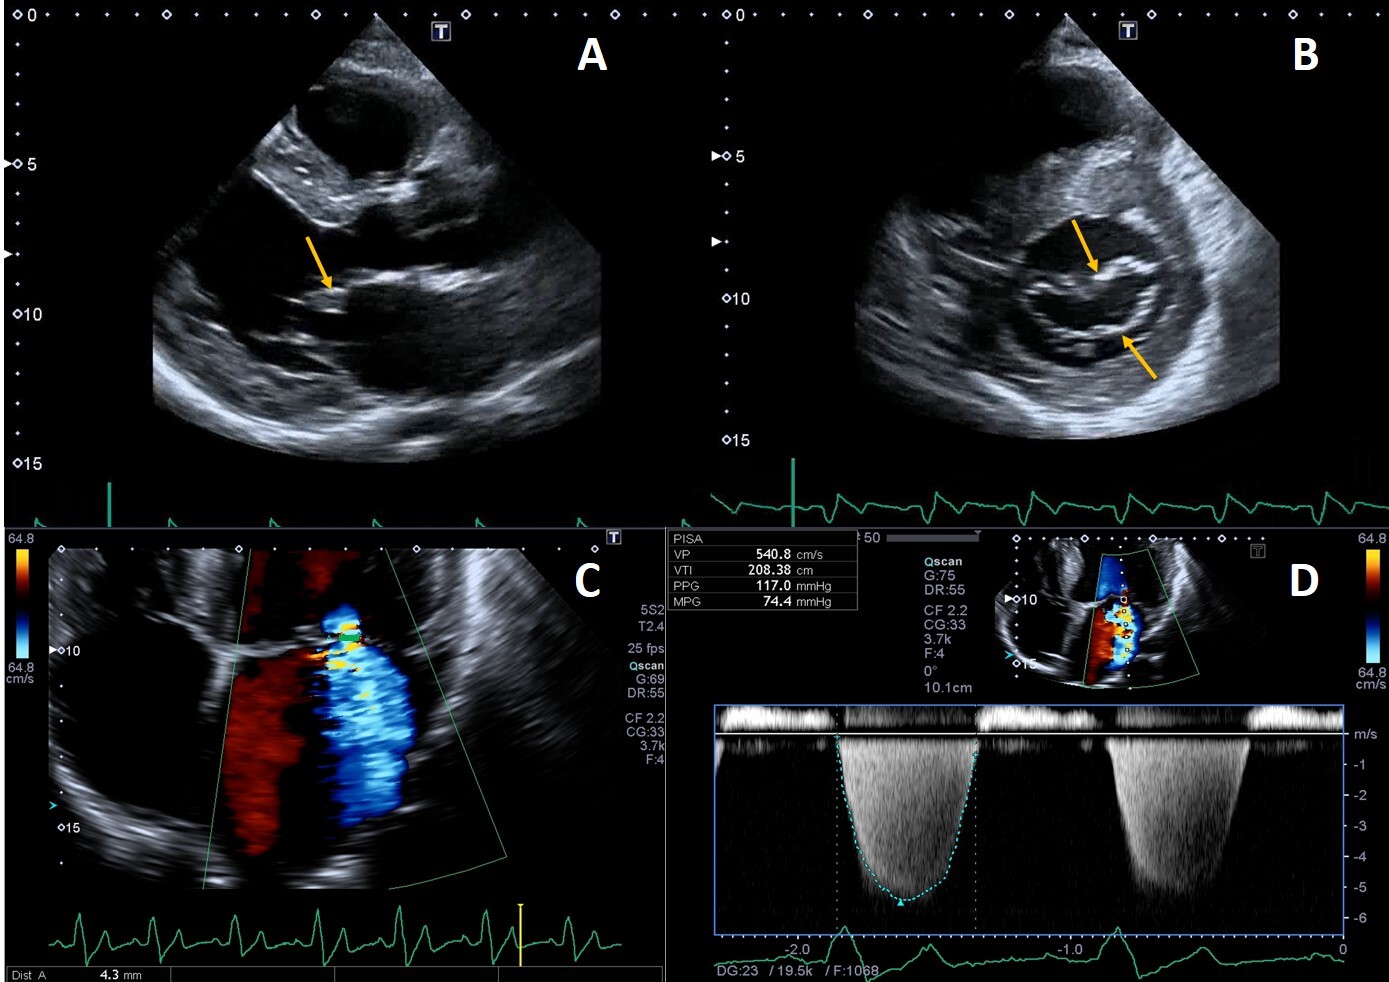

Deposition of glycolipids has been histologically reported in all four heart valves [74]. Leaflet thickening and redundancy are commonly encountered (Fig. 4), affecting the mitral and aortic valves in up to 57% and 47% of patients, respectively [15].

Fig. 4.Example of valvular heart involvement in Fabry Cardiomyopathy. (A, B) Parasternal long-axis and short-axis views showing thickened mitral valve leaflets (arrows). (C) Color Doppler four chamber view focused on the mitral valve, the green line represents the vena contracta width (4.3 mm) suggestive of moderate mitral regurgitation. (D) CW Doppler across the mitral valve.

Mild mitral and aortic regurgitation are frequently detected on echocardiography, while moderate or greater valvular regurgitation is rare and infrequently lead to clinically significant outcomes. Mitral valve prolapse was described as a frequent finding in the past [75] but this was not confirmed recently [76], likely due to implementation of stricter diagnostic criteria [9]. We recently described a case of isolated chordal rupture, which occurred without valve leaflet prolapse, in a patient with Fabry cardiomyopathy. We speculated that in this case chordal rupture could be due to sub-valvular apparatus storage of glycosphingolipids rather than fibro-elastic deficiency [77]. Valvular stenosis is rarely described, even if a case of rapidly progressive aortic stenosis has been reported, and the author proposed that it could have been caused by severe calcification of the aortic valve, as a consequence of valve thickening due to FD or both processes that finally potentiated each other [78].